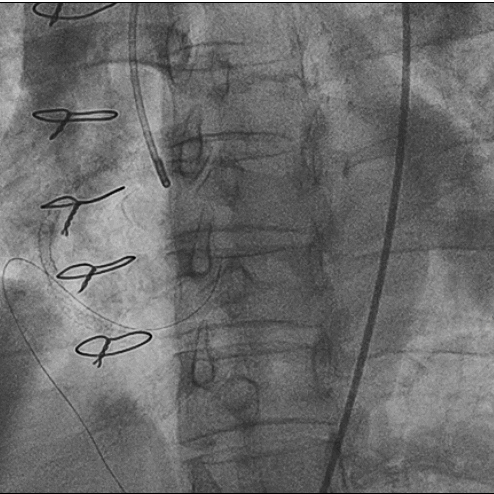

造影图:

LM呈鸟嘴样狭窄,

LAD为迂曲弥漫性病变,中段最重处狭窄80%,曾搭桥已闭塞。RCA曾植入支架,中段支架内反复再狭窄。